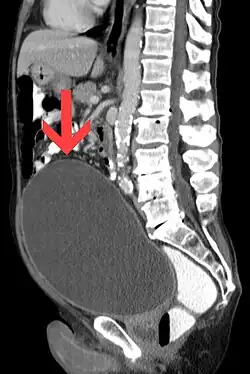

| Urinary retention with greatly enlarged bladder as seen by CT scan. | |